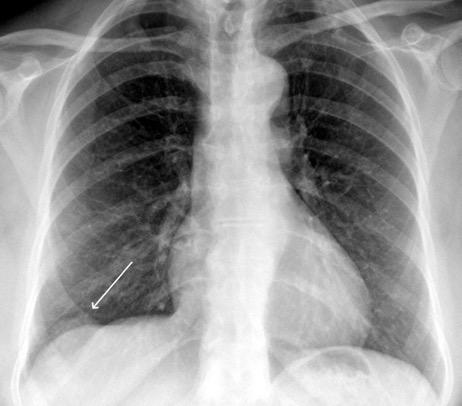

Tromboembolismo pulmonar Diafragma elevado 20%

Consolidación por Infarto pulmonar. (TEP)